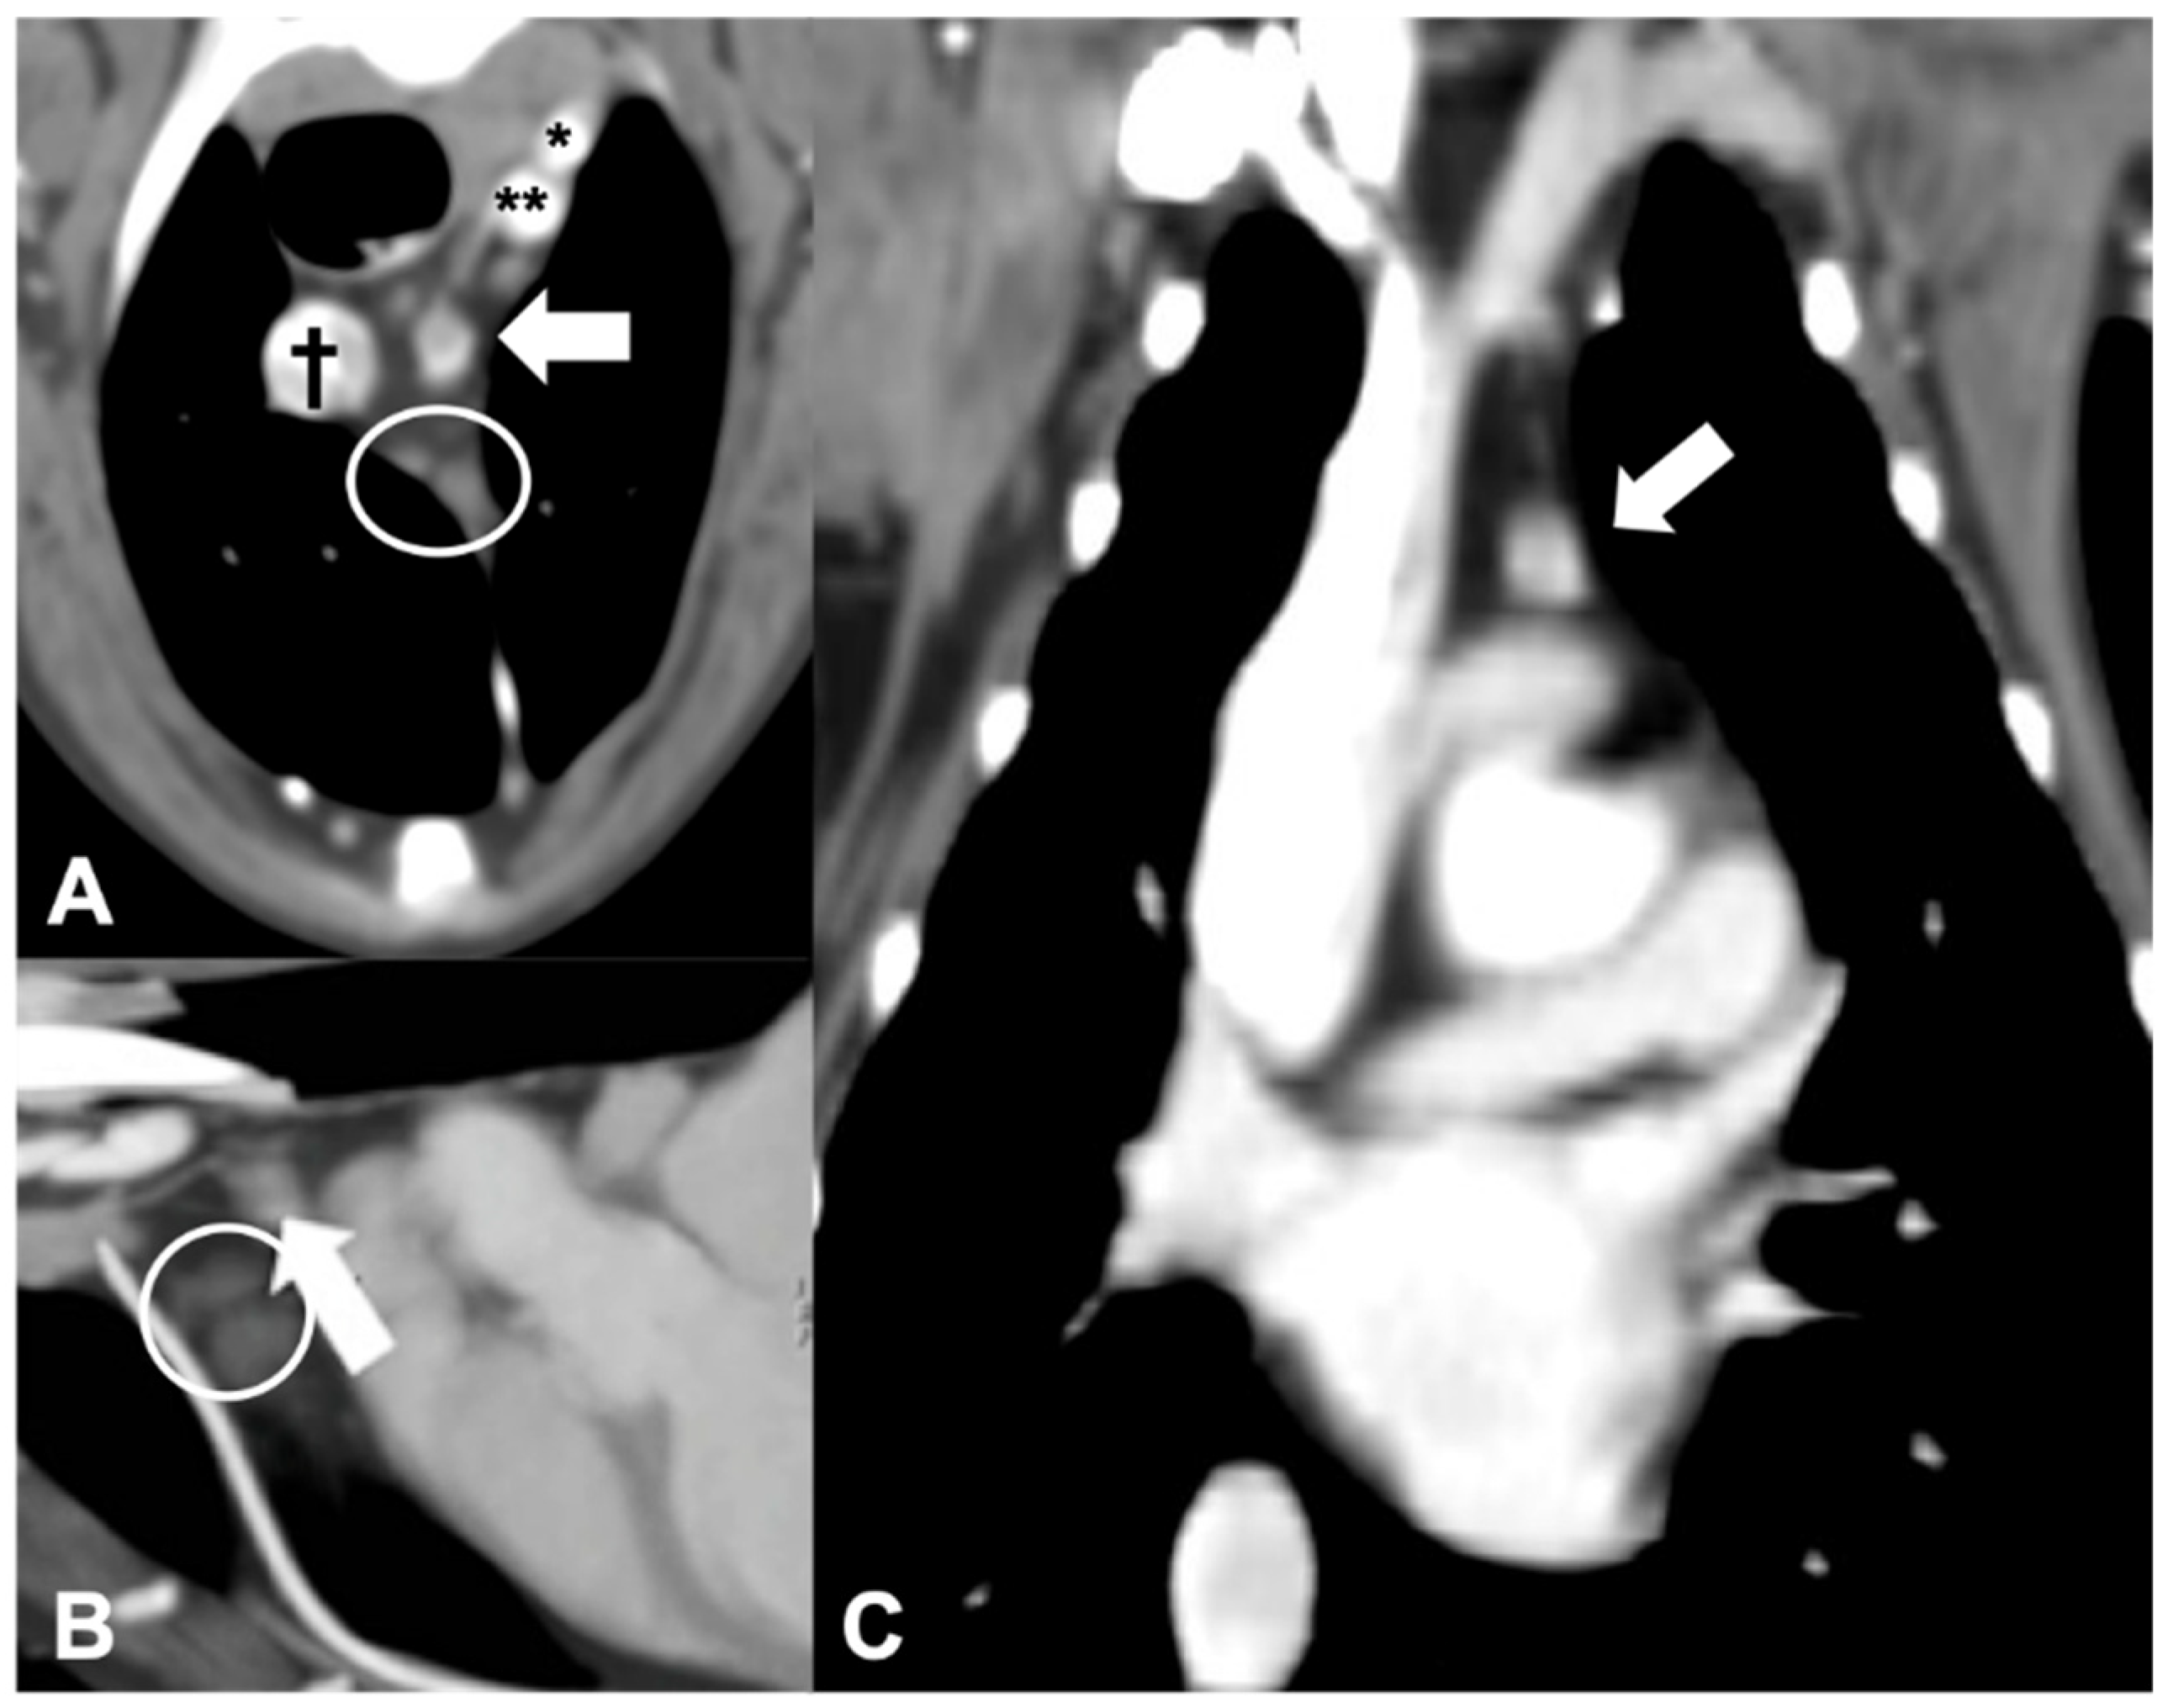

Figure 5.

CT appearance of an ectopic parathyroid gland adenocarcinoma. Post-contrast transverse (A), sagittal (B), and dorsal (C) CT reconstruction images of a dog with diagnosed parathyroid gland adenocarcinoma (arrow) at the level of the cranial mediastinum. † = cranial vena cava; * = left subclavian artery; ** = brachiocephalic trunk. Note the cranial mediastinal lymph nodes (within the circle).